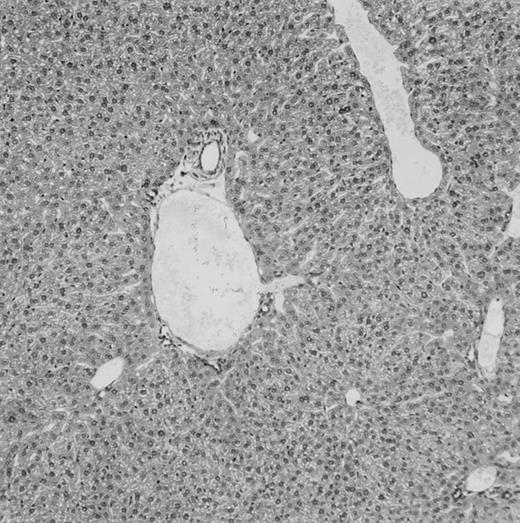

(C) B6 mice receiving FVB BM plus EpΔTK T cells and treated with GCV. (D) B6 mice receiving FVB BM plus EpΔTK T cells, treated with GCV, and developing a late onset GVHD (day 54).

Protection from GVHD was slightly less efficient in the group receiving EpΔTK CD3+ T cells. The survival rate was 79% at day 60 and 67% at day 120 (Fig 2B). However, two different outcomes must be distinguished. On the one hand, a majority of mice behaved as GCV-treated animals receiving EpTK T cells. They were apparently healthy, presented no skin lesions during a 120-day observation period, and showed complete donor-type hematologic reconstitution. There were no histological signs of GVHD in the spleen or liver (Fig 4C).